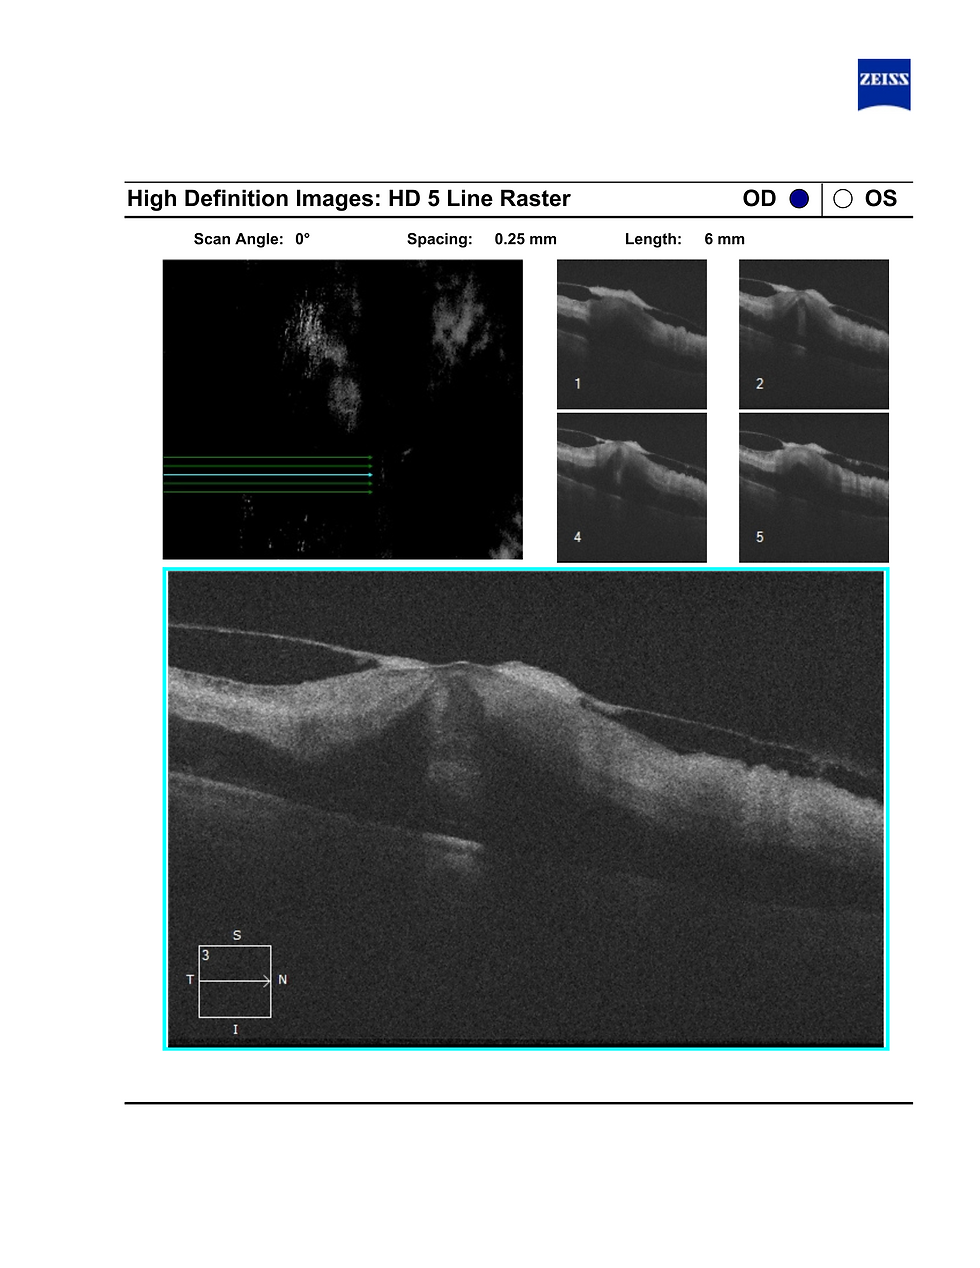

After this I advised right eye OCT (5-liner) where you could see there was macular edema. Based on this, the best management is to go for an intravitreal anti-VEGF injection.